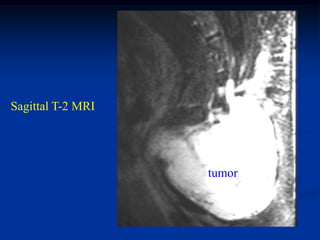

Sagittal T-2 MRI